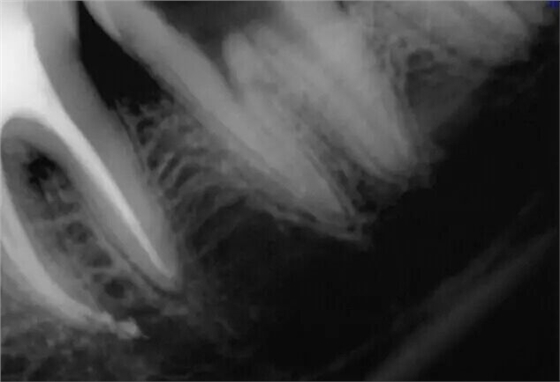

取出斷針時的X片

然后根充